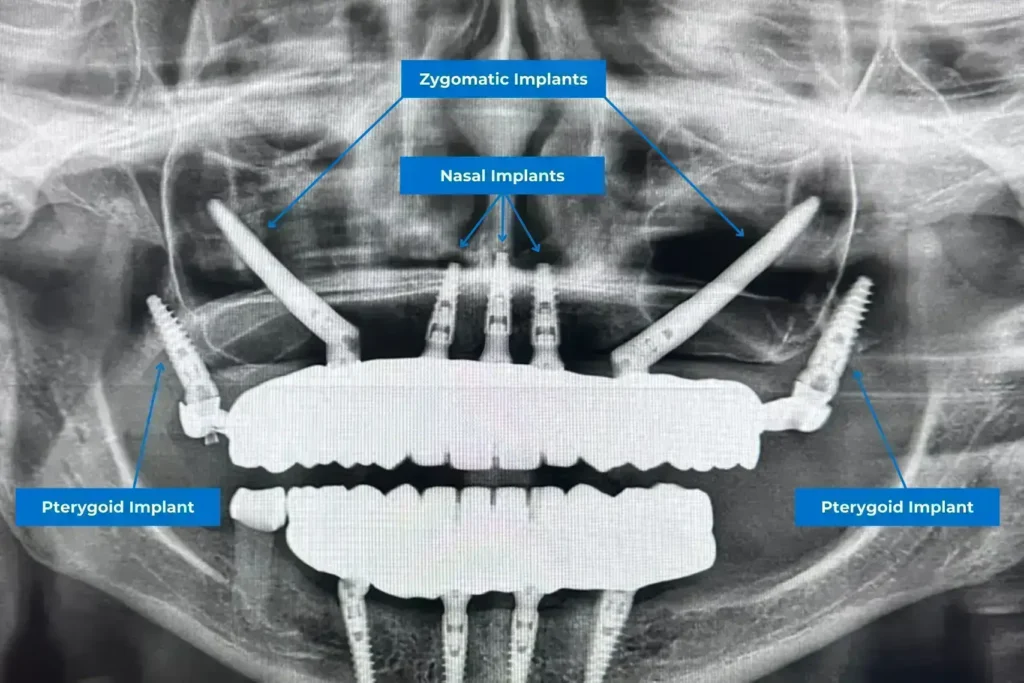

Les implants nasaux ne sont pas toujours une solution autonome. Leur plus grande force réside souvent dans leur complémentarité avec d’autres types d’implants avancés. Ils constituent un soutien antérieur idéal et peuvent être combinés efficacement avec les implants zygomatiques, qui s’ancrent dans l’os de la pommette, ou les implants ptérygoïdiens, placés à l’arrière de la mâchoire. Cette approche hybride est particulièrement bénéfique pour les patients présentant des pertes osseuses extrêmes sur l’ensemble de la mâchoire supérieure. En combinant ces techniques, il est possible de créer une fondation robuste et complète pour une prothèse dentaire fixe qui répartit uniformément les pressions masticatoires, assurant ainsi une stabilité et une longévité optimales. Dentale Albania excelle dans la mise en œuvre de ces stratégies complexes pour offrir une réhabilitation complète.

Implants Nasaux, Zygomatiques, et Ptérygoïdiens : Comprendre les Solutions pour une Mâchoire Supérieure Restaurée

La compréhension des distinctions entre les différents types d’implants dentaires avancés est cruciale pour déterminer la solution la plus adaptée à votre situation. Les implants nasaux, les implants zygomatiques et les implants ptérygoïdiens sont toutes des options innovantes pour les cas de perte osseuse sévère, mais elles ciblent des zones anatomiques et des besoins spécifiques. Chez Dentale Albania, nos spécialistes évalueront précisément votre condition pour recommander la stratégie optimale, souvent en combinant ces techniques.

Absolument, oui. Bien que les implants nasaux et zygomatiques soient des solutions avancées pour les cas de perte osseuse sévère au maxillaire supérieur, leurs zones d’ancrage et leurs objectifs principaux sont distincts. Les implants nasaux sont conçus pour apporter un soutien dans la partie antérieure de la mâchoire supérieure. Ils s’ancrent spécifiquement dans l’os nasal, traversant la cavité nasale pour trouver un os cortical dense et stable. Leur rôle est d’assurer une stabilité pour les dents de devant et de supporter les forces verticales.

En revanche, les implants zygomatiques, comme leur nom l’indique, utilisent l’os zygomatique, plus communément appelé l’os de la pommette, comme point d’ancrage. Ces implants sont beaucoup plus longs et sont insérés avec un angle spécifique pour contourner les sinus maxillaires, offrant un soutien dans les régions latérales et postérieures de la mâchoire supérieure. Ils sont particulièrement efficaces pour la restauration des molaires et prémolaires, ainsi que pour le soutien d’une arcade complète. Alors que les nasaux se concentrent sur l’avant, les zygomatiques couvrent l’arrière, fournissant ainsi une alternative lorsque l’os alvéolaire traditionnel est insuffisant. Ces deux techniques offrent des solutions là où d’autres échouent, mais elles sont complémentaires plutôt que mutuellement exclusives.

Oui, absolument. La combinaison des implants nasaux avec d’autres types d’implants avancés est non seulement possible, mais souvent la stratégie la plus efficace pour les patients présentant une perte osseuse extrême sur l’ensemble de la mâchoire supérieure. Pour une réhabilitation complète de l’arcade maxillaire, où un soutien stable est nécessaire à la fois à l’avant et à l’arrière, les implants nasaux peuvent être associés aux implants zygomatiques et/ou aux implants ptérygoïdiens. Par exemple, les implants nasaux peuvent fournir un ancrage robuste pour les dents antérieures, tandis que les zygomatiques ou ptérygoïdiens stabilisent la prothèse dans les régions latérales et postérieures.

Cette approche hybride crée une fondation incroyablement solide et résiliente pour une prothèse fixe, assurant une répartition égale des pressions masticatoires et une longévité maximale du traitement. Elle permet de surmonter les défis anatomiques les plus sévères et de restaurer une fonction et une esthétique complètes. Nos spécialistes à Dentale Albania possèdent l’expertise nécessaire pour planifier et exécuter ces protocoles complexes, offrant une solution globale et durable pour votre sourire.